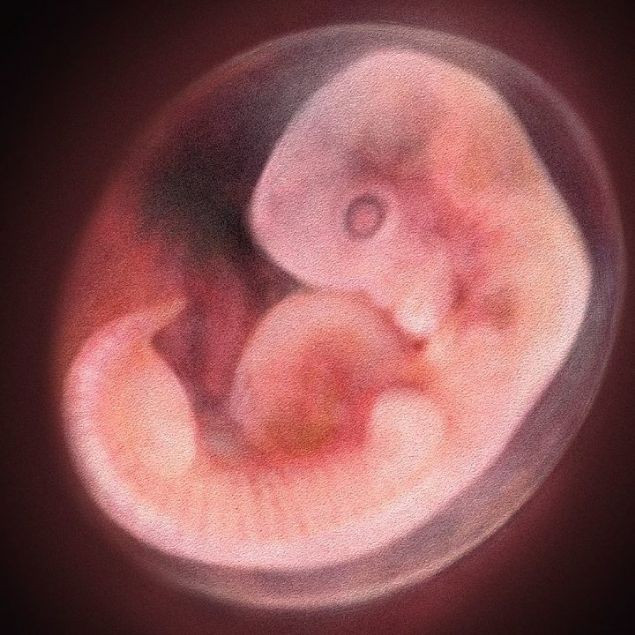

Bilim insanları ilk kez insan embriyosunun genlerini değiştirerek bebeğin büyüdüğünde geçirmesi muhtemel olan ölümcül hastalıkları engelledi.